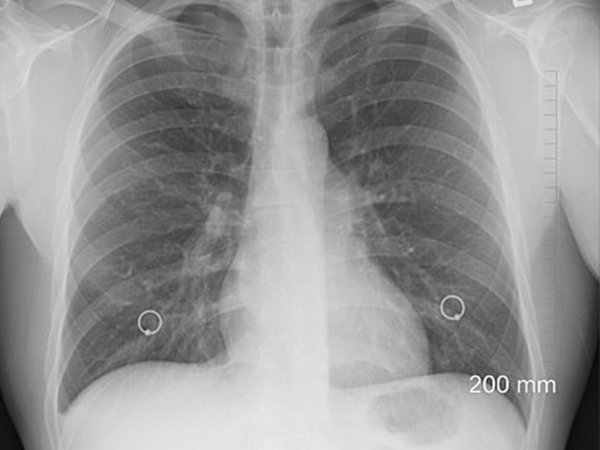

நுரையீரலில் நீர் தேக்கம் என்பது பல்வேறு உடல் உபாதைகளுக்கான அறிகுறியாக இருக்க முடியும். நிமொனியாவின் சில வடிவங்களுக்கு இது ஒரு பொதுவான அறிகுறியாகப் பார்க்கப்படுகிறது. ஆனால் நுரையீரல் புற்றுநோய் காரணமாகவும் இந்த நீர் தேக்கம் ஏற்படலாம்.

அல்லது மிகவும் அரிதாக இடைத்தோலியப் புற்று நோய் எனப்படும் மெசொதேலியோமாவின் காரணமாக இருக்க முடியும். அதனால் நுரையீரலில் நீர் தேக்கம் உள்ளதற்கான அறிகுறிகள் தென்பட்டால், உடனடியாக மருத்துவ ஆலோசனைப் பெறுவது நல்லது.

பெரும்பாலும் ஒரு எக்ஸ்ரே அல்லது EKG எடுத்துப் பார்த்து, எந்த இடத்தில் திரவம் சேர்ந்துள்ளது என்பது பரிசோதனையில் கண்டறியப்படும். இதன் மூலமாக, முன்கூட்டியே நுரையீரல் புற்றுநோய் ஏற்படக் கூடிய வாய்ப்பு களையப்படும்.